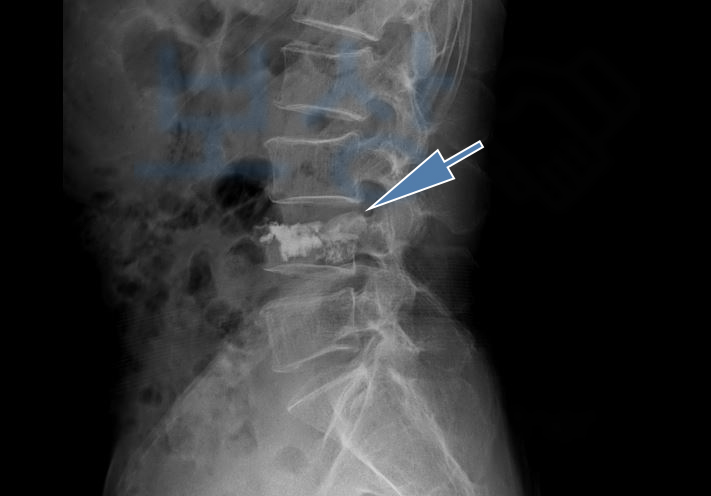

골절의 모습이 좋지않아 추후 큰 후유증을 야기할 수 있어 골시멘트술을 받으셨는데요, 조@@님께서 받은 시술은

골절된 척추체를 목표로

의료용 시멘트를 주사하는

척추의 안정성을 위한 시술입니다. 골시멘트시술을 받은 이후